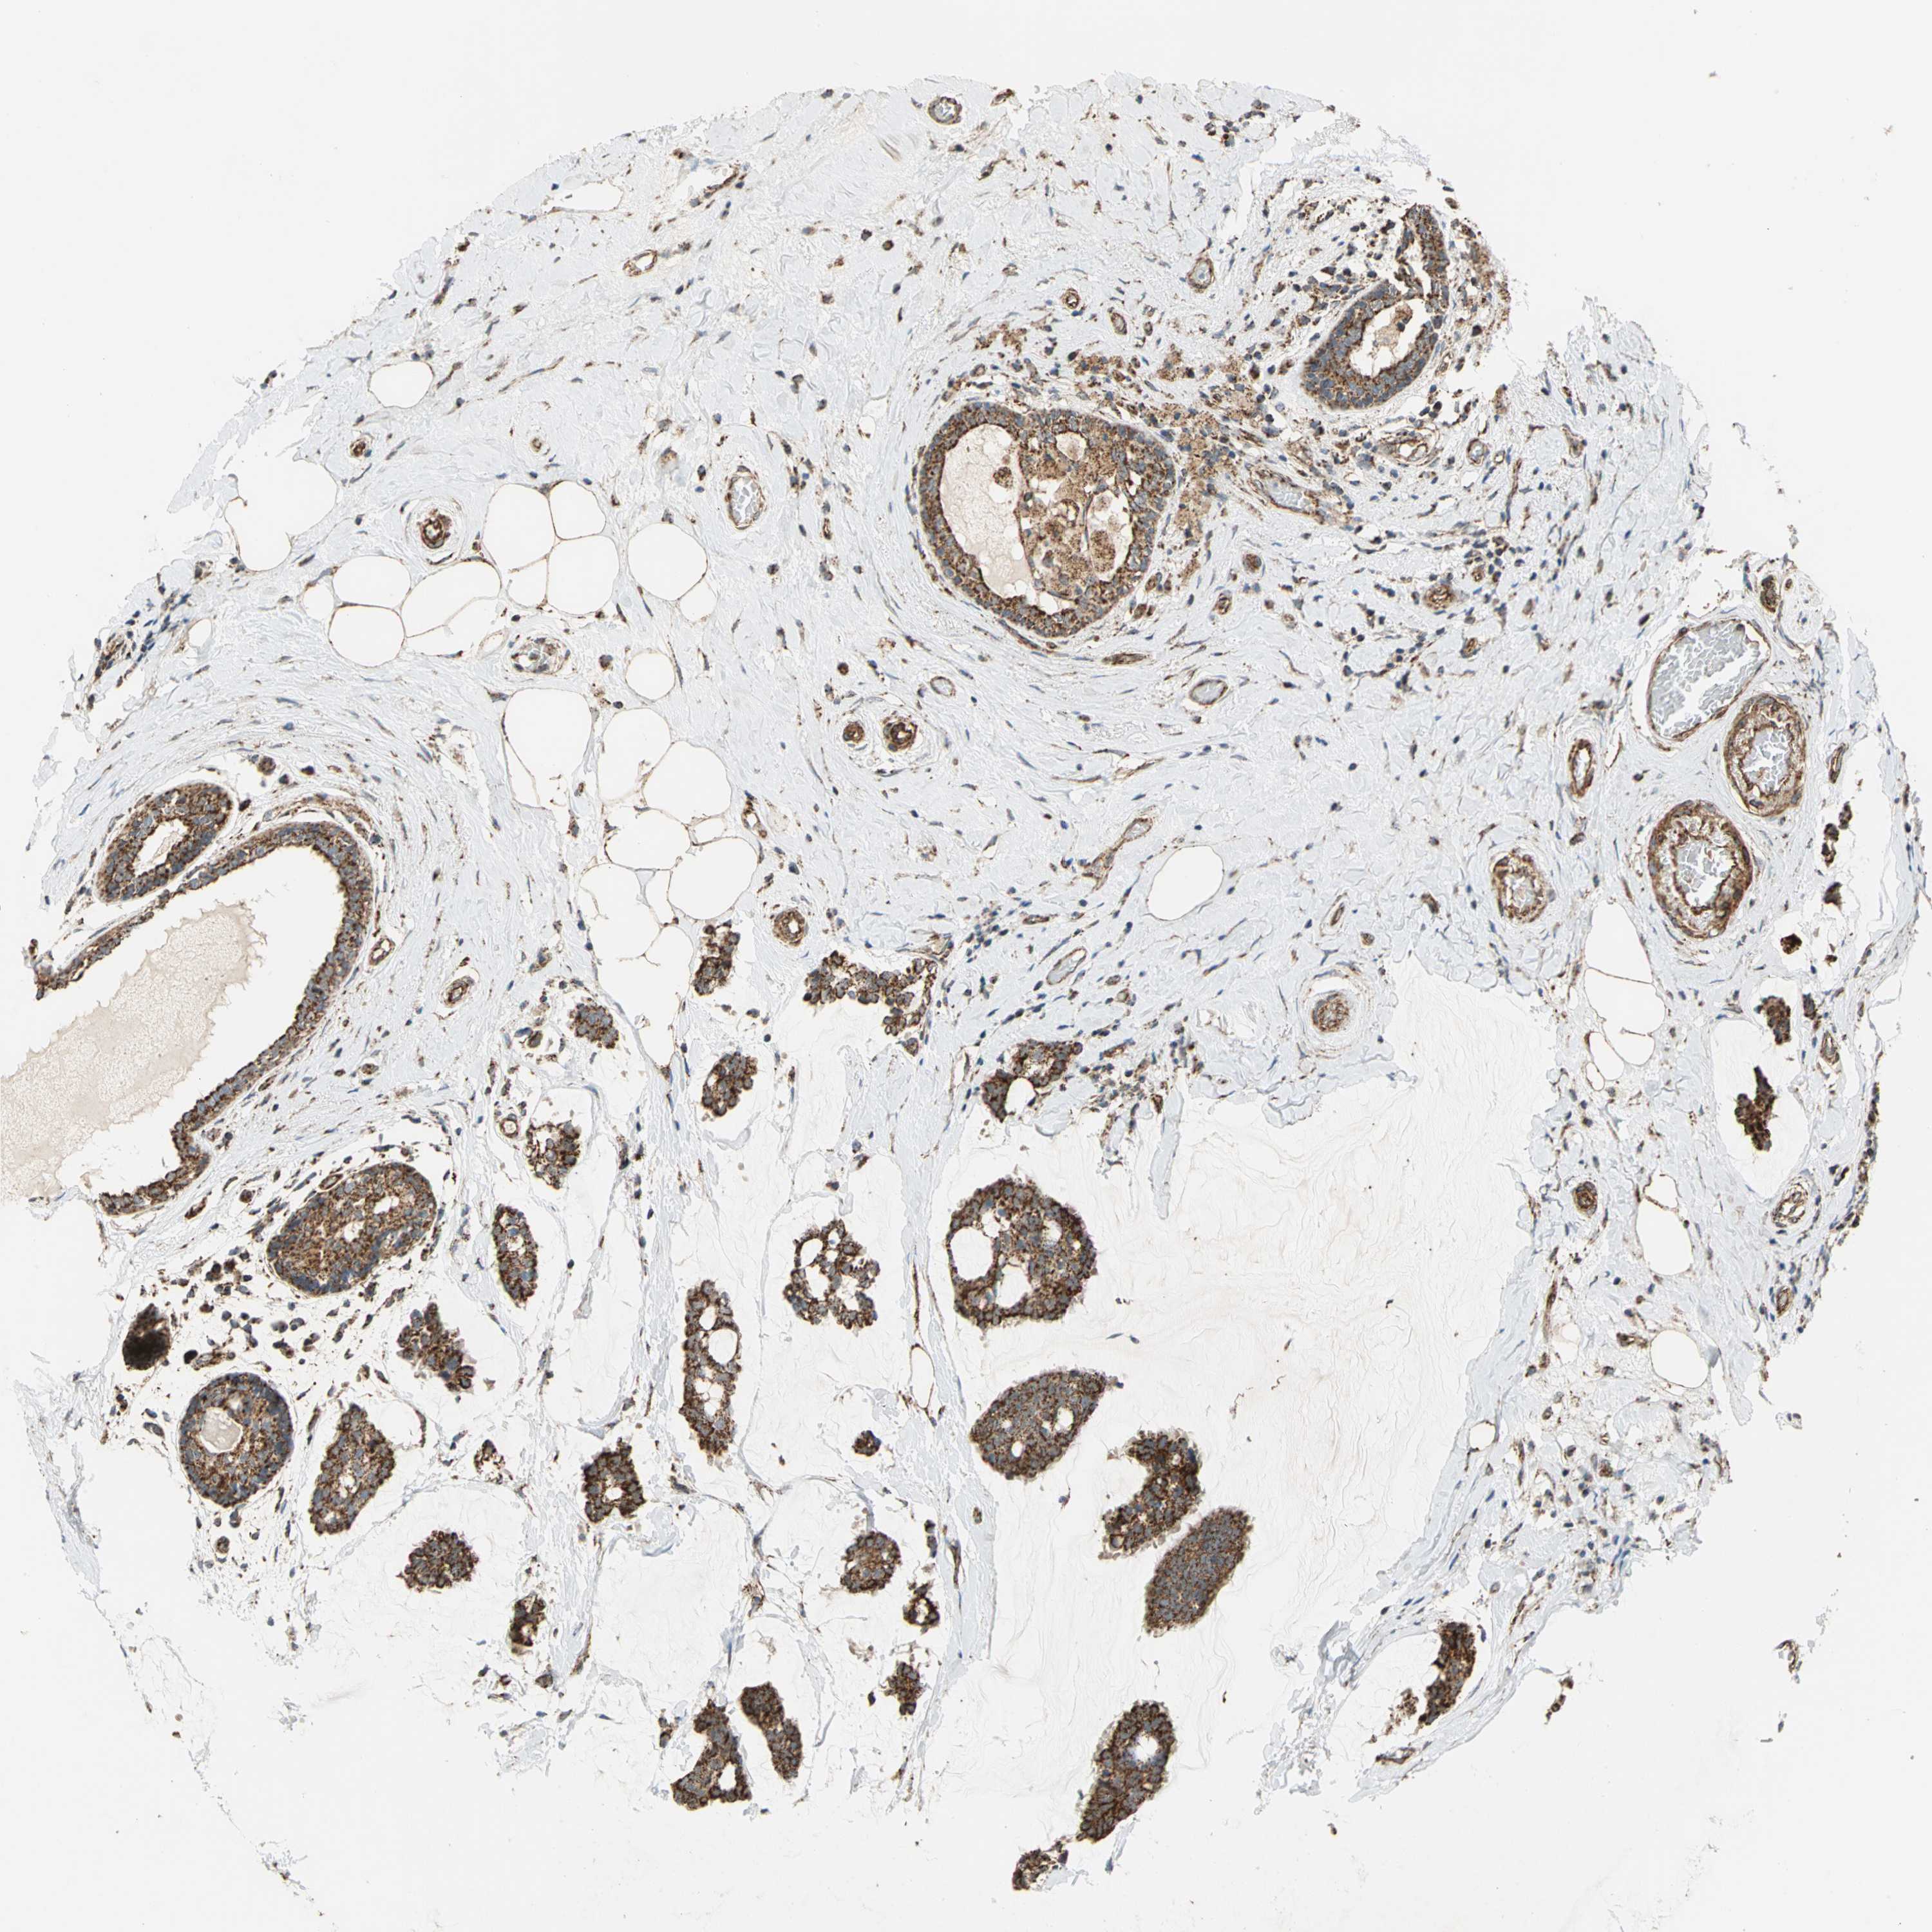

BRCA TCGA BRCA VALIDATION PROTEIN EXPRESSION